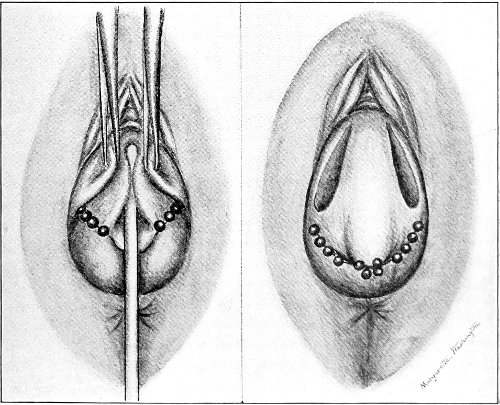

The secondary operation is performed at any time after cicatrization has occurred—often many years after the receipt of the injury. This operation is at present one of the commonest in gynecology, because the injury is not detected, is neglected, or is improperly repaired after labor. In the secondary operation an anesthetic is necessary. The mucous membrane must be removed or denuded on the posterior wall and about the mouth of the vagina, in order that the lacerated structures may be brought again in apposition. The denudation is best made by means of scissors curved on the flat (Figs. 24 and 25).

The strip of mucous membrane to be removed is picked up with a tenaculum (Fig. 26) or with tissue forceps 65 (Fig. 27); the scissors are placed with the blades parallel to the surface to be denuded, and the strip is cut away evenly, in one piece if possible. A similar contiguous strip is removed, and so on until the necessary surface is bare. Sponges in holders (Fig. 28) or continuous irrigation may be used to remove blood.

Silver wire and silkworm gut are the best sutures in the operation of perineorrhaphy.

The suture is conveniently attached to the needle by means of a silk carrier (Fig. 31).

The sutures may be fastened by passing the ends through a perforated shot which is slipped down to the line of union and compressed by the shot-compressor (Fig. 32). All blood should be carefully removed from the surfaces that are brought together. The sutures should only be sufficiently tense to produce accurate apposition. A light gauze drain should be introduced in the vagina, and should be removed in forty-eight hours. Afterward one vaginal douche of about a quart of warm bichloride solution (1:2000) should be administered every day. After the douche the labia should be separated and the vagina carefully dried by cotton held in dressing-forceps. Except in those cases in which the sphincter ani is involved, the bowels may be moved on the second or third day. The woman should stay in bed for two weeks, at the end of which time the sutures should be removed. 67 She should avoid heavy lifting, long standing, and bicycle- or horseback-riding for two months after the operation. Constipation should always be avoided. Coitus may be resumed six weeks after operation.